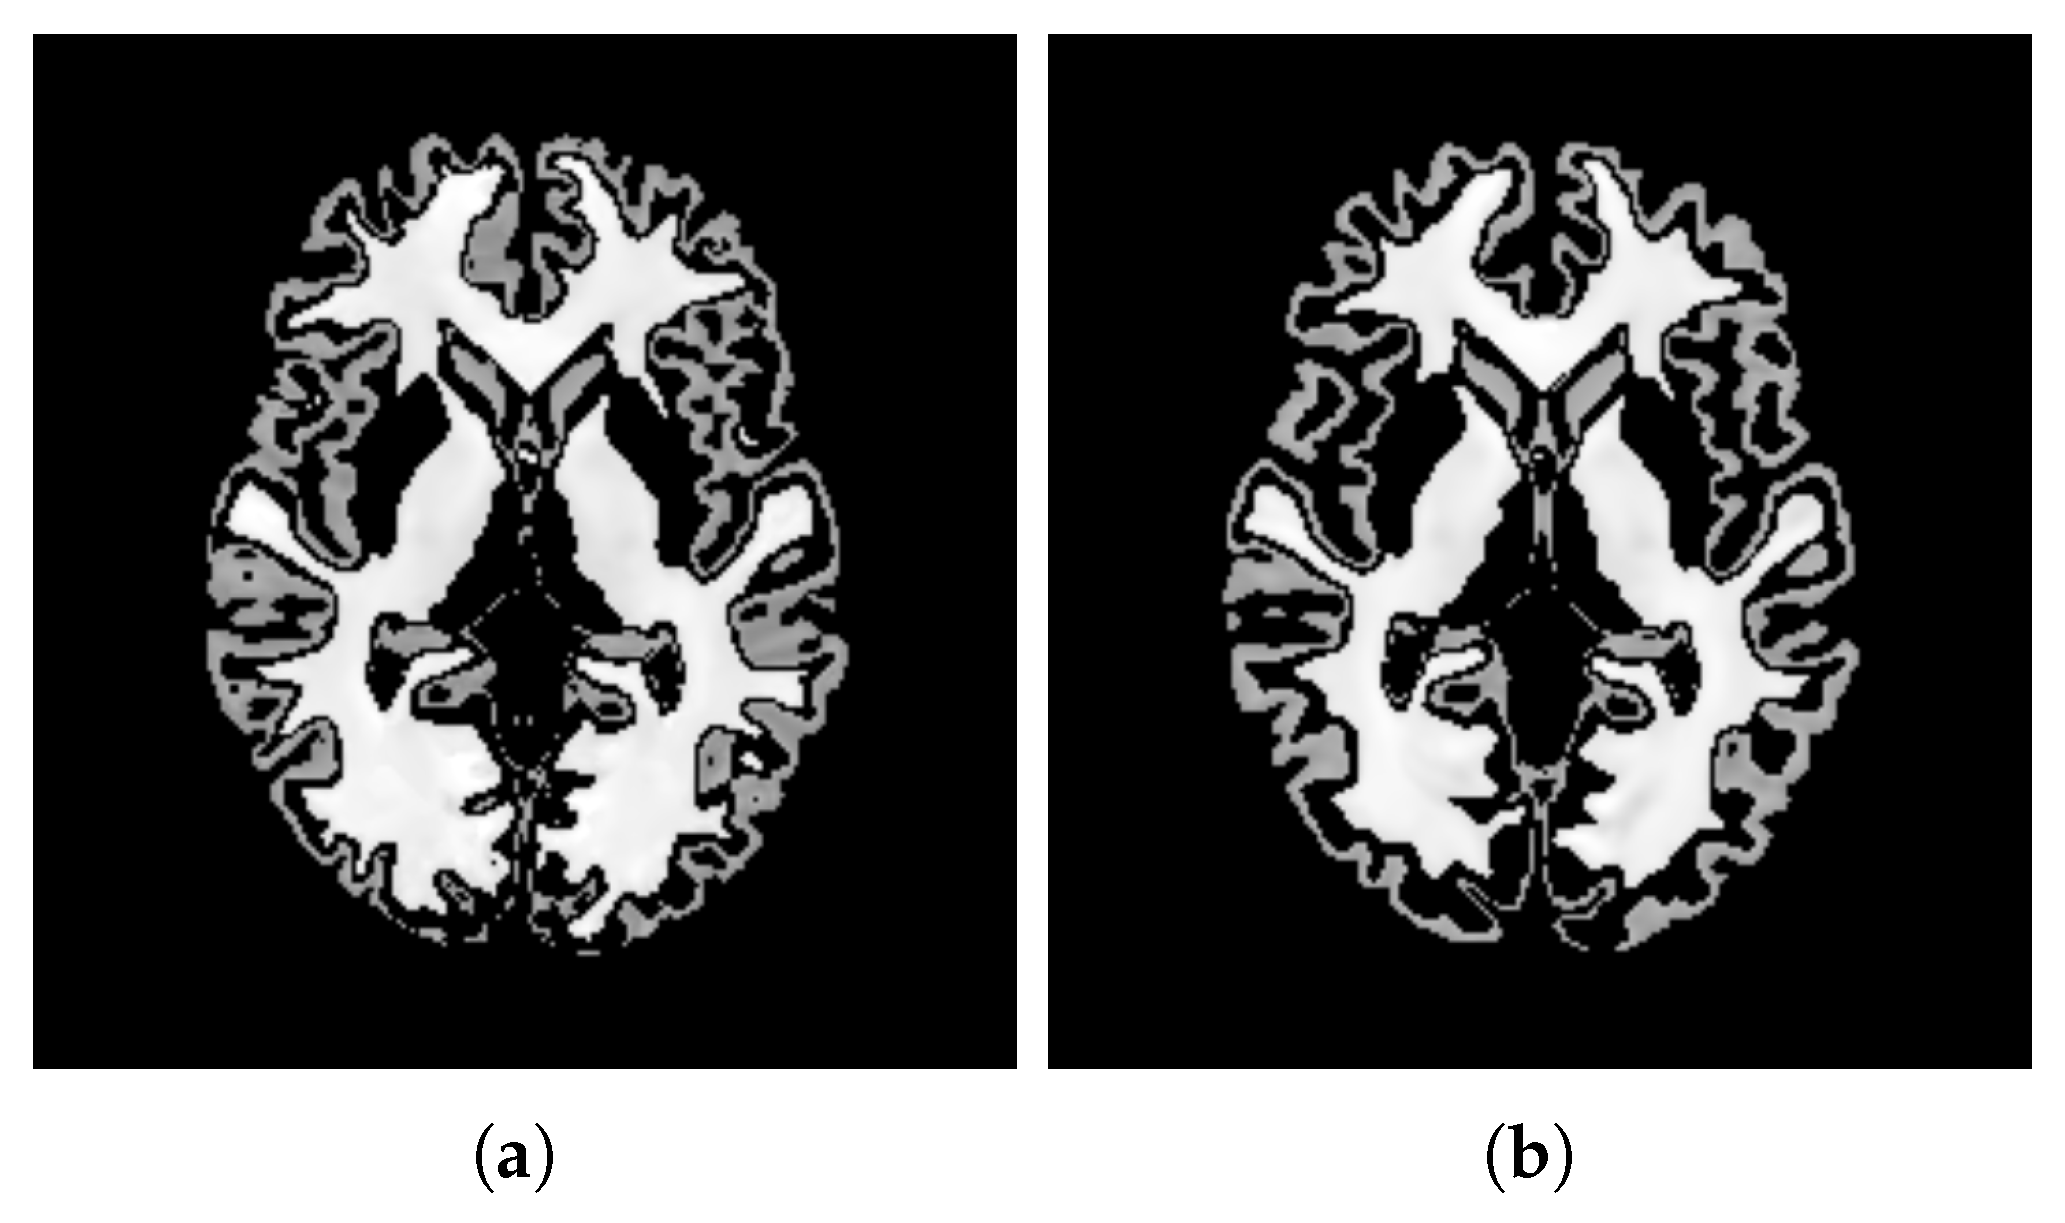

- ContrastTo evaluate the contrast between white matter (WM) and gray matter (GM) of the templates, we used the Normalized Michelson Contrast [92]. This metric provides a standardized measure of contrast by comparing the maximum intensity of WM to the minimum intensity of GM. To identify WM and GM voxels, we utilized the BrainSuite tool (version 23a) [93] to segment the templates into different tissue types. This allowed us to isolate voxels corresponding to pure WM and GM, excluding those with other tissue types. It is worth noting that we utilized the BrainSuite tool [93] on a local machine, not within the Google Colaboratory environment [57]. This metric, Normalized Michelson Contrast (), quantifies the contrast between WM and GM; higher values indicate greater contrast:where is the maximum intensity value within the WM voxels, and is the minimum intensity value within the GM voxels.

- ContrastTable 4 presents the values calculated for the pure WM and GM regions of the templates generated using the patch-based () and voxel-based () methods. Figure 15 visualizes these pure tissue regions in both templates. As shown in the table, the value for (0.418) is higher than that of (0.393), indicating higher contrast in the former. This suggests that the patch-based approach yields a template with enhanced contrast between these tissues compared with the voxel-based averaging method.